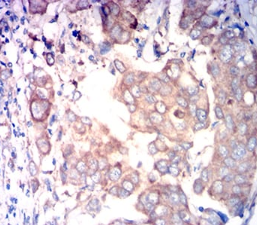

FAP Mouse Monoclonal antibody[1H12F]

The protein encoded by this gene is a homodimeric integral membrane gelatinase belonging to the serine protease family. It is selectively expressed in reactive stromal fibroblasts of epithelial cancers, granulation tissue of healing wounds, and malignant cells of bone and soft tissue sarcomas. This protein is thought to be involved in the control of fibroblast growth or epithelial-mesenchymal interactions during development, tissue repair, and epithelial carcinogenesis. Alternatively spliced transcript variants encoding different isoforms have been found for this gene. [provided by RefSeq, Apr 2014]

Species Reactivity :   Human

IHC    1/200 - 1/1000